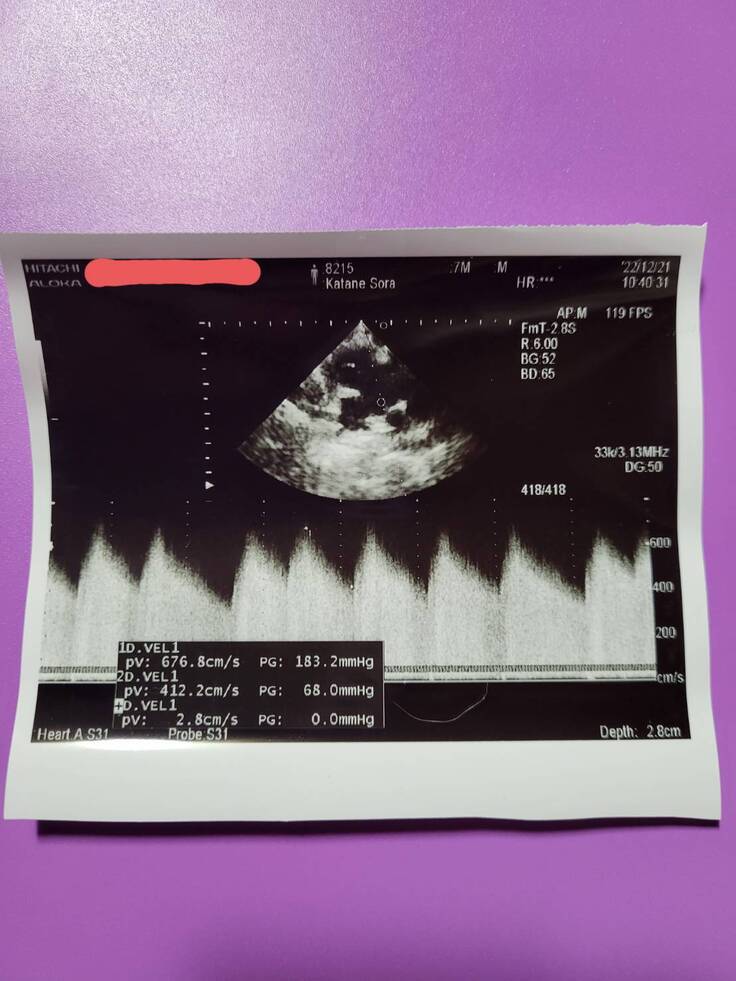

現在は、心不全や肺が固くならないように、心臓の負担を減らすため、診断が出てから毎日薬を飲んでいます。

2週間に1回、エコー検査をするため通院しています。

▲心臓のエコー写真です。

個人情報のため病院名は伏せさせて頂きます。掲載許可はいただいています。